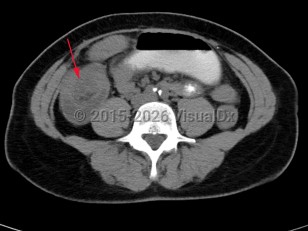

Intussusception is a telescoping or invagination of a part of the intestine into the lumen of an adjacent segment. Intussusception can present with variable severity. It can present with bowel ischemia and perforation with need for emergent surgical intervention, or it can present as relaxing / remitting abdominal pain of unclear etiology with intermittent symptoms and no signs of systemic illness. Jejunojejunal, jejunoileal, ileoileal, ileocolonic, and colocolonic are all types of intussusception that can occur, with the majority involving the small intestine.

Intussusception occurs in children and adults. It is the most common cause of bowel obstruction in children, where it presents with sudden onset of acute abdominal pain and inconsolability, and at times with emesis, a palpable abdominal mass, or hematochezia. Tucking knees into the torso is consoling in some instances. In pediatrics, intussusception is most commonly due to viral illnesses, with mesenteric lymphadenopathy creating a lead point to trigger intussusception. Tumors, polyps, Meckel diverticulum, or postsurgical adhesions are additional causes that can trigger intussusception.

Initial management requires ensuring hemodynamic stability, as many patients are dehydrated, and assessing concern for bowel perforation, which could require broad-spectrum antibiotics and urgent surgical intervention. Air or barium enemas can be both diagnostic and therapeutic. However, intussusception will frequently recur, in which case surgical resection is often required. Further imaging (ie, small bowel x-ray series, CT or MRI abdomen) can be utilized to identify the etiology if it is unknown based on presenting symptoms and a barium / air enema.